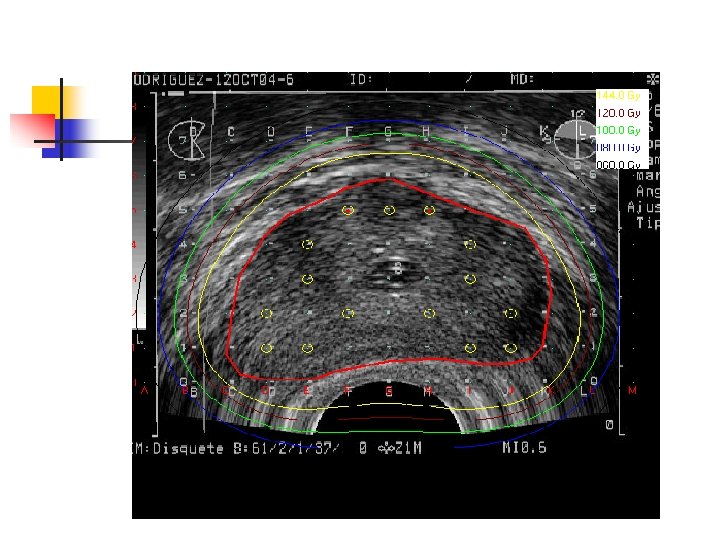

Radioterapia n n n Paciente de 70 años No antecedentes personales PSA elevado (10 ng/ml) Punción Biópsica Prostática AP: Adenocarcinoma Gleason 6 Paciente plantea en la consulta que desea tener hijos.

Actuarial prostate-specific antigen relapse-free survival outcomes for 81 -Gy intensitymodulated radiation therapy, according to risk group. (From Zelefsky MJ, Chan H, Hunt M, et al. Long-term outcome of high dose intensity modulated radiation therapy for patients with clinically localized prostate cancer. J Urol 2006; 176: 1415– 1419,

Foto del Primer Caso Clínico tratado en el Hospital de Clínicas el 12 de febrero de 2002